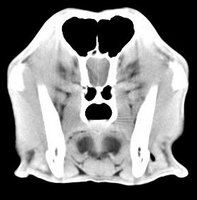

imágenes de TC en el perro | ||||||||||

ejemplo de imágenes de TC en el perro. Nótese la celulitis en la región parotídea izquierda | ||||||||||

Tomografía computarizada helicoidal |